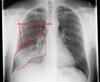

CXR β†’ Locate effusion β†’ CXR or Chest CT β†’ Best: Chest CT

↓

Perform Thoracentesis

——————————–

| |

Clear fluid Cloudy fluid

↓ Pleural Protein ↑ Pleural Protein

↓ Pleural LDH ↑ Pleural LDH

Transudative Effusion Exudative Effusion

↑ PCWP β†’ CHF β†’ Obtain Pleural Glucose

↓ Albumin β†’ Nephrotic ↓ Pleural Glucose

↔ Albumin β†’ Cirrhosis β†’ Causes:

β†’ Malignancy (abnormal cytology)

β†’ Empyema (culture +, ↓↓ pH)

β†’ Autoimmune (ANA/RF+)

β†’ Tuberculosis (AFB stain+)

β†’ Normal Pleural Glucose

β†’ ↑ Pleural TG β†’ Chylothorax

β†’ ↑ Pleural RBCs β†’ Hemothorax

β†’ ↑ Pleural Amylase

β†’ Pancreatitis

β†’ Esophageal rupture